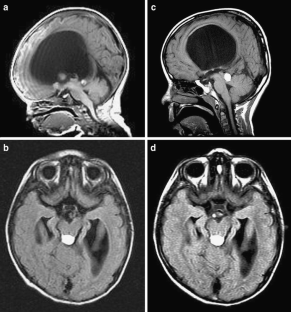

Fig. 1